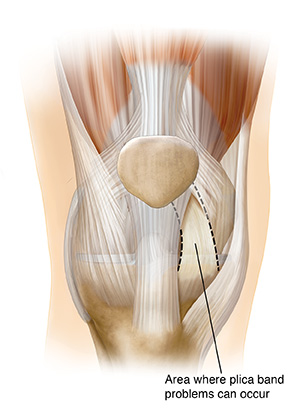

Plica syndrome

Plica bands are tissue fibers that some people have near the kneecap. They often cause no problems. But sometimes they can become irritated or inflamed.